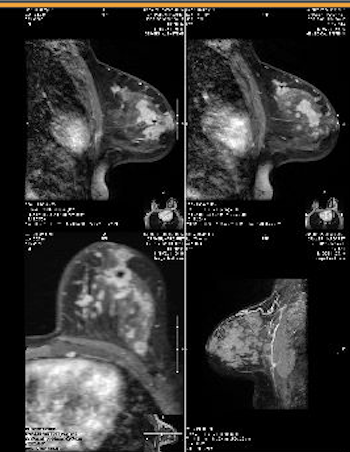

Patient two weeks postpartum with right breast cancer and abnormal lymph node visualized on MRI.

Patient six months postpartum with new lump right breast that was not well visualized on mammogram but appeared distinctly on MRI.